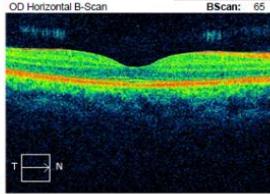

On examination, his visual acuity in the right eye was 6/4.5 while his left eye was counting fingers. His intraocular pressures were $16\mathrm{mmHg}$ and $10\mathrm{mmHg}$ in his right and left eye respectively. He had a grade III left relative afferent pupillary defect (RAPD). Whilst he had full range of eye movement, there was pain on moving his left eye. His left optic nerve was grossly swollen with a macular star (figure 1). There was no anterior chamber inflammation or vitritis. Optical coherence of the retinal nerve fibre layer (OCT RNFL) assessment showed an average RNFL thickness of $481\mu \mathrm{m}$, with peripapillary subretinal fluid extending to the fovea (figure 2). Automated perimetry demonstrated an early central scotoma in the left visual field with mean deviation (MD) -4.35 dB. He had a normal right ocular examination and ancillary investigations. Clinical examination and investigations were consistent with left neuroretinitis.

Figure 2: Zeiss OCT macular $512 \times 128$ cube (a) and disc RNFL $200 \times 200$ cube (b) of both eyes. The left eye demonstrates optic nerve head oedema (b) with peripapillary and foveal subretinal fluid (a).